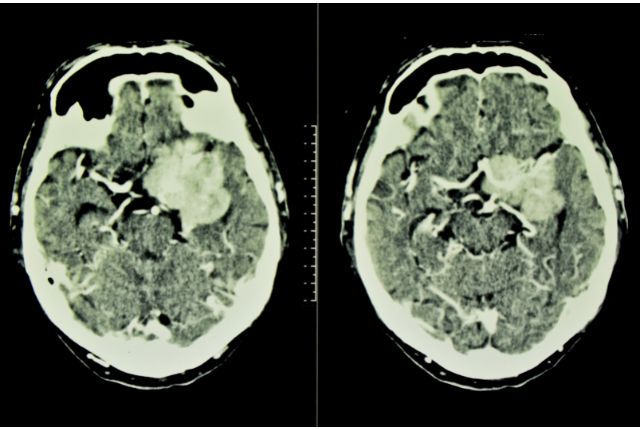

Comment diagnostiquer un méningiome : IRM, scanner, PET-Scan ?

L’IRM (Imagerie par Résonance Magnétique) est l’examen de référence pour le diagnostic du méningiome ; celui-ci est réalisé généralement en injectant au patient un produit de contraste afin de bien visualiser les structures du cerveau et des méninges. D’autres examens d’imagerie médicale, comme le scanner ou le PET-Scan, peuvent également être envisagés pour étudier la localisation et la vascularisation du méningiome. Une biopsie cérébrale peut également être envisagée dans certains cas. D’autres examens, comme un bilan ophtalmique, un électroencéphalogramme ou encore un bilan neuropsychologique peuvent enfin compléter le diagnostic (notamment si une intervention est envisagée).